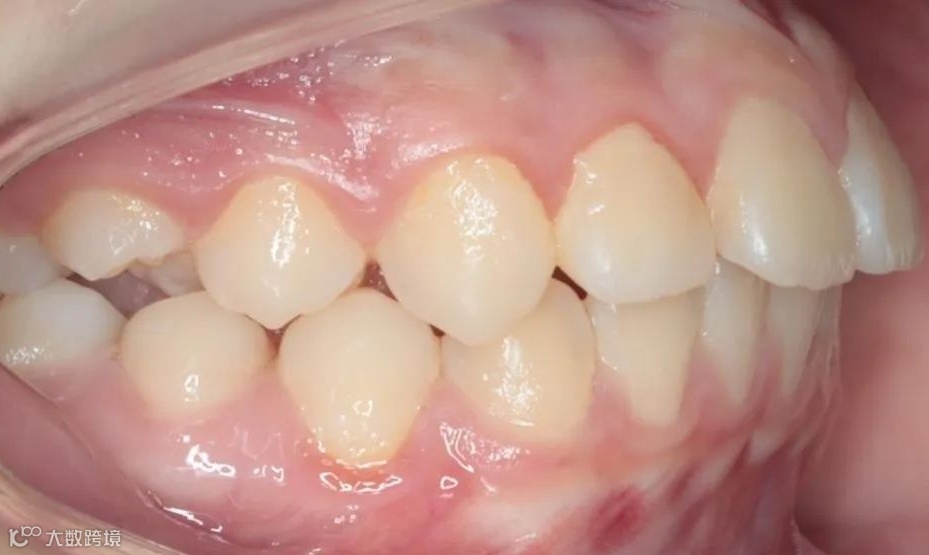

治疗后右侧咬𬌗相

治疗后正面咬𬌗相

治疗后左侧咬𬌗相

患儿戴用Twin-Block矫治器,在引导下颌向前的同时扩宽上颌牙弓,内收上前牙。